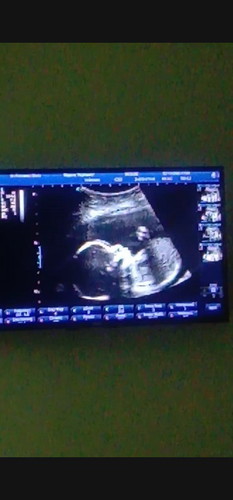

สาวน้อย เดือนมีนาคม64

แม่บ้านใหนคลอดเดือนมีนาคม64 บ้างคะ ไ้ด้เพศไรบ้างคะ บ้านนี้ได้สาวน้อยสมใจเลยค่ะ